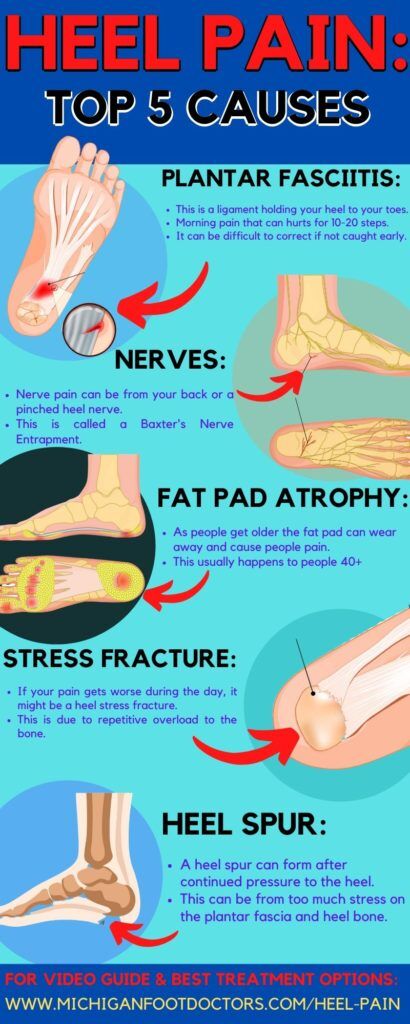

Pain In Bottom Of Heel Causes Symptoms Best Home Treatment

Heel Pain Treatment in Payson Heel Spurs Springville Orem UT

Heel Pain Treatment Montgomery County TX Heel Injury The

Heel spurs Symptoms risk factors and treatment

Common Conditions Causing Heel Pain top, Heel Pain Causes Treatment and When to See a Doctor top, Plantar Fasciitis and Bone Spurs OrthoInfo AAOS top, Pain In The Back Of The Heel May Mean You Have Other Problems top, What is Causing My Heel Pain NeuroSpine Surgical Consultants top, Plantar Fasciitis Treatment options for your painful heel s top, Common Conditions Causing Heel Pain top, Plantar fasciitis treatment symptoms and causes healthdirect top, Heel Pain Treatment Specialist Top Foot Doctor Podiatrist NYC top, Heel Pain causes and treatment plantar fasciitis diagnosis and treatment top, Is my heel pain from plantar fasciitis Gundersen Health top, Sever s Disease Heel Pain OrthoInfo AAOS top, Heel Pad Pain Signs Causes Diagnosis Treatment top, Heel Pain 5 Common Causes Elliott M. Perel DPM FACFAS Podiatrist top, Multi pronged Heel Pain Management Podiatry Clinic in SG top, 10 Most Likely Causes of Heel Pain Symptoms and Treatments top, Heel Pain when Running Matthew Boyd Physio top, Main Causes of Back of Heel Pain in North Seattle Foot and Ankle top, Heel Pain Stirling Central Podiatry top, How to Relieve HEEL PAIN in Seconds top, Heel pain or plantar fasciitis Treatment exercises and causes top, Causes and Treatment of Heel Pain Dr. John Chrabuszcz OrthoGeorgia top, Severs Disease Sever s Disease Treatment Sydney top, Medanta Heel Pain Causes Prevention and Treatment top, Plantar Fasciitis Causes Symptoms Treatments and More top, Heel Pain Causes Symptoms Treatment Foot Pain Explored top, Plantar Fasciitis Symptoms Causes Treatment Options top, Plantar fasciitis Symptoms and causes Mayo Clinic top, Heel pain Symptoms Causes. Prevention and Treatment HealthShots top, Pain In The Back Of The Heel May Mean You Have Other Problems top, Foot Pain Causes Treatment top, Heel pain RunBionic top, Heel Pain Cleveland Foot And Ankle Consultants top, Heel Heel Pain Specialist Pain International Clinic Dr top, Do you suffer from painful heels Active Care Podiatry top, Heel pain and Rigidus Shellharbour Podiatry Your Local Podiatrists top, Plantar Fasciitis Physical Therapy for Heel Pain ATI top, Patient Basics Heel Pain 2 Minute Medicine top, Plantar heel pain Health High Performance Australia top, A Stabbing Heel Pain top, Posterior heel pain Chelsea and Westminster Hospital NHS top, Pain In Bottom Of Heel Causes Symptoms Best Home Treatment top, What is Plantar heel pain Learn everything about it here top, Heel Pain Treatment in Payson Heel Spurs Springville Orem UT top, Heel Pain Treatment Montgomery County TX Heel Injury The top, Heel spurs Symptoms risk factors and treatment top, What s Causing My Heel Pain Quick Pain Relief Performance Health top, Plantar Fasciitis A Painful Heel Hughston Clinic top, Heel Pain Relief Heel Pain Causes Dr. Scholl s top, Cracked Heels Causes Symptoms Treatment The Feet People top.

Common Conditions Causing Heel Pain top, Heel Pain Causes Treatment and When to See a Doctor top, Plantar Fasciitis and Bone Spurs OrthoInfo AAOS top, Pain In The Back Of The Heel May Mean You Have Other Problems top, What is Causing My Heel Pain NeuroSpine Surgical Consultants top, Plantar Fasciitis Treatment options for your painful heel s top, Common Conditions Causing Heel Pain top, Plantar fasciitis treatment symptoms and causes healthdirect top, Heel Pain Treatment Specialist Top Foot Doctor Podiatrist NYC top, Heel Pain causes and treatment plantar fasciitis diagnosis and treatment top, Is my heel pain from plantar fasciitis Gundersen Health top, Sever s Disease Heel Pain OrthoInfo AAOS top, Heel Pad Pain Signs Causes Diagnosis Treatment top, Heel Pain 5 Common Causes Elliott M. Perel DPM FACFAS Podiatrist top, Multi pronged Heel Pain Management Podiatry Clinic in SG top, 10 Most Likely Causes of Heel Pain Symptoms and Treatments top, Heel Pain when Running Matthew Boyd Physio top, Main Causes of Back of Heel Pain in North Seattle Foot and Ankle top, Heel Pain Stirling Central Podiatry top, How to Relieve HEEL PAIN in Seconds top, Heel pain or plantar fasciitis Treatment exercises and causes top, Causes and Treatment of Heel Pain Dr. John Chrabuszcz OrthoGeorgia top, Severs Disease Sever s Disease Treatment Sydney top, Medanta Heel Pain Causes Prevention and Treatment top, Plantar Fasciitis Causes Symptoms Treatments and More top, Heel Pain Causes Symptoms Treatment Foot Pain Explored top, Plantar Fasciitis Symptoms Causes Treatment Options top, Plantar fasciitis Symptoms and causes Mayo Clinic top, Heel pain Symptoms Causes. Prevention and Treatment HealthShots top, Pain In The Back Of The Heel May Mean You Have Other Problems top, Foot Pain Causes Treatment top, Heel pain RunBionic top, Heel Pain Cleveland Foot And Ankle Consultants top, Heel Heel Pain Specialist Pain International Clinic Dr top, Do you suffer from painful heels Active Care Podiatry top, Heel pain and Rigidus Shellharbour Podiatry Your Local Podiatrists top, Plantar Fasciitis Physical Therapy for Heel Pain ATI top, Patient Basics Heel Pain 2 Minute Medicine top, Plantar heel pain Health High Performance Australia top, A Stabbing Heel Pain top, Posterior heel pain Chelsea and Westminster Hospital NHS top, Pain In Bottom Of Heel Causes Symptoms Best Home Treatment top, What is Plantar heel pain Learn everything about it here top, Heel Pain Treatment in Payson Heel Spurs Springville Orem UT top, Heel Pain Treatment Montgomery County TX Heel Injury The top, Heel spurs Symptoms risk factors and treatment top, What s Causing My Heel Pain Quick Pain Relief Performance Health top, Plantar Fasciitis A Painful Heel Hughston Clinic top, Heel Pain Relief Heel Pain Causes Dr. Scholl s top, Cracked Heels Causes Symptoms Treatment The Feet People top.